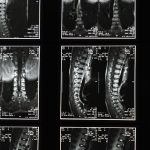

La sciatique est souvent causée par une pression sur le nerf sciatique due à des facteurs tels que les hernies discales, les pincements nerveux ou des problèmes de colonne vertébrale. Lorsque ces compressions se produisent, la douleur peut irradier de la région lombaire jusqu’à une jambe. Il est essentiel d’adopter des mesures préventives et de savoir comment réagir lors des crises.

Tout d’abord, l’information sur la sciatique et ses causes est cruciale. La douleur sciatique peut résulter de diverses pathologies vertébrales, notamment une hernie discale, une sténose spinale ou un syndrome du piriforme. Comprendre ce qui déclenche votre douleur peut vous permettre de mieux éviter les mouvements et les positions qui aggravent vos symptômes. Évitez de vous pencher en avant ou de porter des charges lourdes, autant que possible.

Une IRM ou une radiographie est généralement recommandée pour évaluer l’état de la colonne vertébrale.

Une IRM ou une radiographie est généralement nécessaire pour confirmer la cause de la sciatique.